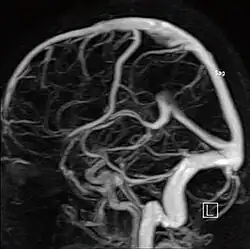

МР-ангиография

Артерии головного мозга

Магнитно-резонансная ангиография (МР-ангиография, МРА) — метод получения изображения кровеносных сосудов при помощи магнитно-резонансного томографа. Исследование проводится на томографах с напряжённостью магнитного поля не менее 0.3 Тл. Метод позволяет оценивать как анатомические, так и функциональные особенности кровотока.